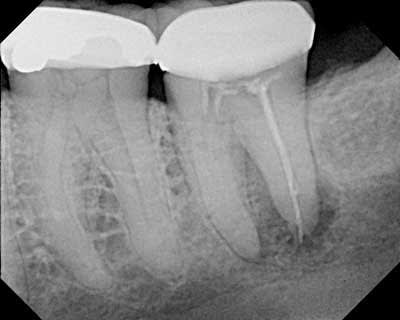

Pennwell.web.400 - Eugenol

Ce qui est intéressant dans ta radio Hoksai c'est de voir que la racine où un certain effort a été fait pour aléser , obturer c'est celle qui est la plus atteinte , la pseudo pulpo aurait mieux marché on dirait .